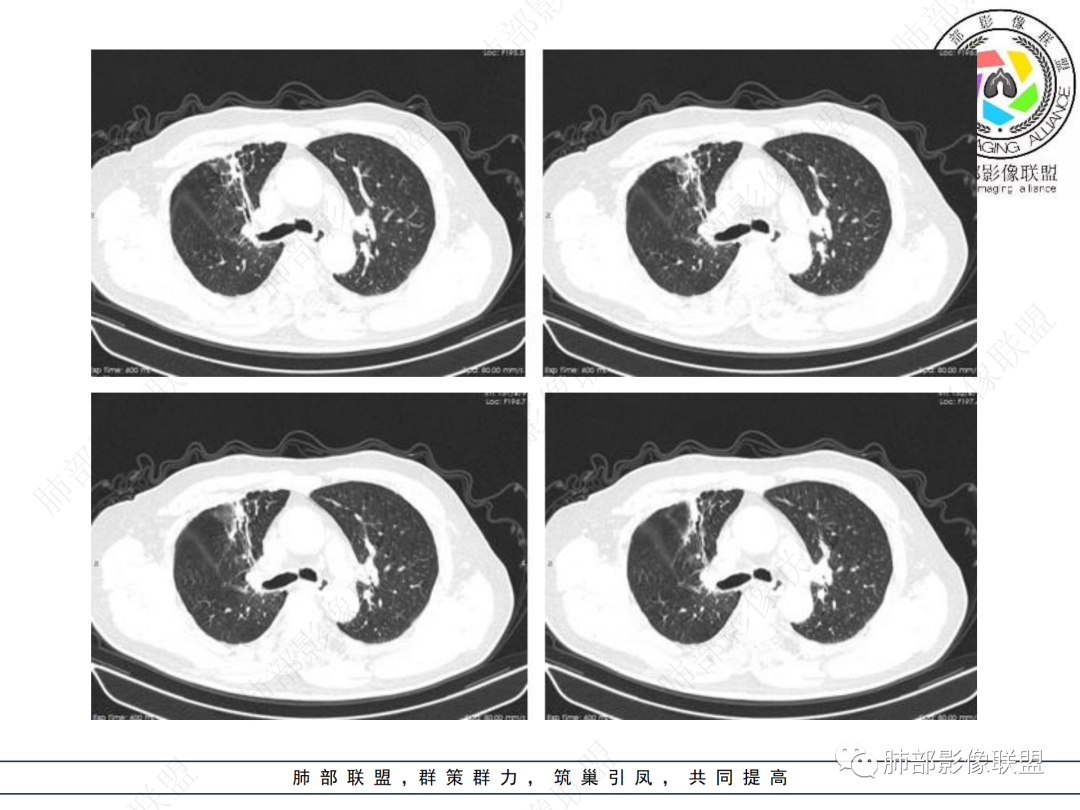

结合本病例,老年男性患者,慢性病程,急性加重,无吸烟史,影像学表现为右肺上叶尖后段斑片实变密度影,整体边界清晰,边缘平直收缩为主,周边散在纤维条索影,内部见支气管内粘液栓,血管影走形正常,没有明显破坏,增强扫描明显强化,缺乏典型分叶毛刺、胸膜改变,病灶也未显示清楚的磨玻璃勾边,病灶大而肺门纵隔未见肿大淋巴结,综合考虑慢性炎性肉芽肿可能性大。但恶性,结核能完全排除吗?我想对临床医生来说还是有很大考验的。

在临床上诊断慢性炎症其实比诊断肿瘤和结核都要棘手,因为病原学找到了结核菌,结合临床,检验,影像等相关资料就可以确诊结核病,活检时发现有肿瘤细胞就可以诊断恶性疾病。但如果没有发现结核菌和肿瘤细胞,结核和肿瘤有时候仍然不能排除,也不宜轻易断定慢性炎,临床还需要治疗,观察,甚至手术切除送大病理。